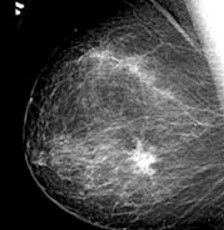

- Birads 5: Kemungkinan keganasan yang sangat tinggi di mana biopsi jaringan sangat disarankan untuk memastikan diagnosis. Temuan khusus dari presentasi kategori 5 adalah mikrokalsifikasi ganas, distorsi arsitektur, margin yang tidak jelas dan tidak teratur, massa terspikulasi

- Birads 6: Kanker yang dikonfirmasi dari biopsi jaringan